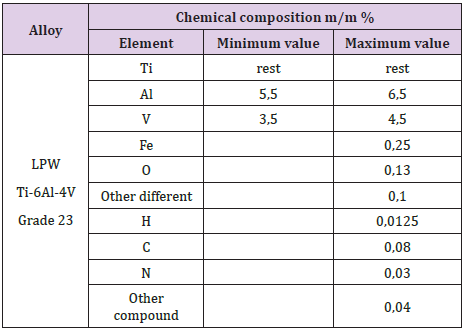

The most widely used titanium alloy for dental implants, prostheses, and other medical devices is Ti-6Al-4V. We used Grade 23 titanium powder for the additive manufacturing of our implants. This material has outstanding corrosion resistance and biocompatibility. LPW Technology Ltd. was the supplier of the metal powder. Table 1 shows the chemical composition of this Ti- 6Al-4V alloy in mass percent.

Subperiosteal implant design started with the processing of CBCT images. Figure 1 shows STL files of the patient’s mandibula, which is the lower jawbone. Figure 2 shows STL file of the patient’s maxilla, which is the upper jawbone. Figure 3 shows the result of virtual planning with the maxilla, mandibula, the designed implant, and denture. The final subperiosteal implant was designed based on CBCT images. Mechanical aspects were also considered in the design process of the titanium framework. Figure 4 shows the STL file of our titanium implant design with its three-dimensional geometry that had been analysed with finite element method.